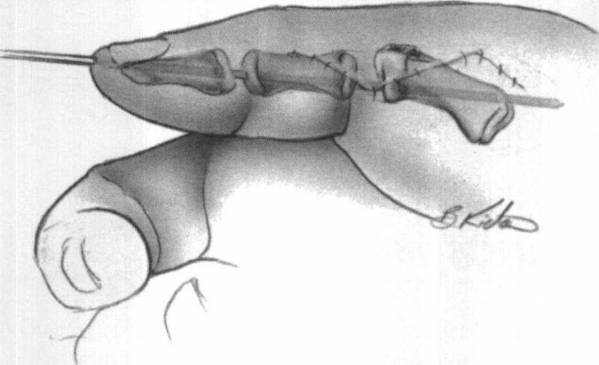

复拇畸形手术治疗的目的是尽可能恢复拇指的正常解剖结构。切除赘生拇指,保留近似正常的拇指。

切除拇指的动力结构和软组织需部分保留利用。

对于孪生拇指畸形,可以进行拼合。

a07355.0026.3.jpg

a07355.0028.3.jpg

a07355.0029.1.jpg

图片来源于网络

绘画是一门艺术

尤其是医学绘画